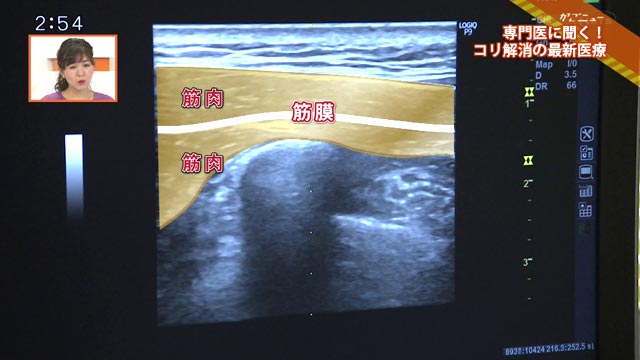

筋膜とはひとつひとつの筋肉をおおっている膜。筋膜と筋膜がくっついてしまっていると肩こりや痛みにつながることが、最新医療で分かってきました。早速筋膜リリースのためのストレッチを教えていただきました。